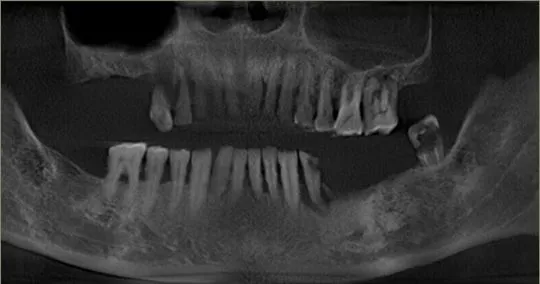

▲粤剧大师卢海潮口腔CT片 缺牙4颗

在好友“阿光”苏志丹和“康婶”黄锦裳的力荐下,卢老来到柏德口腔做种植牙,针对卢老年纪大怕疼痛,德国牙医博士为卢老制定了数字化微创种植方案。

柏德口腔数字化微创种植,运用种植导板精准“导航”,有效避开神经和血管,安全无痛,伤口小于0.5cm,缩短手术时间50%,非常适合年纪大怕疼痛的缺牙朋友。